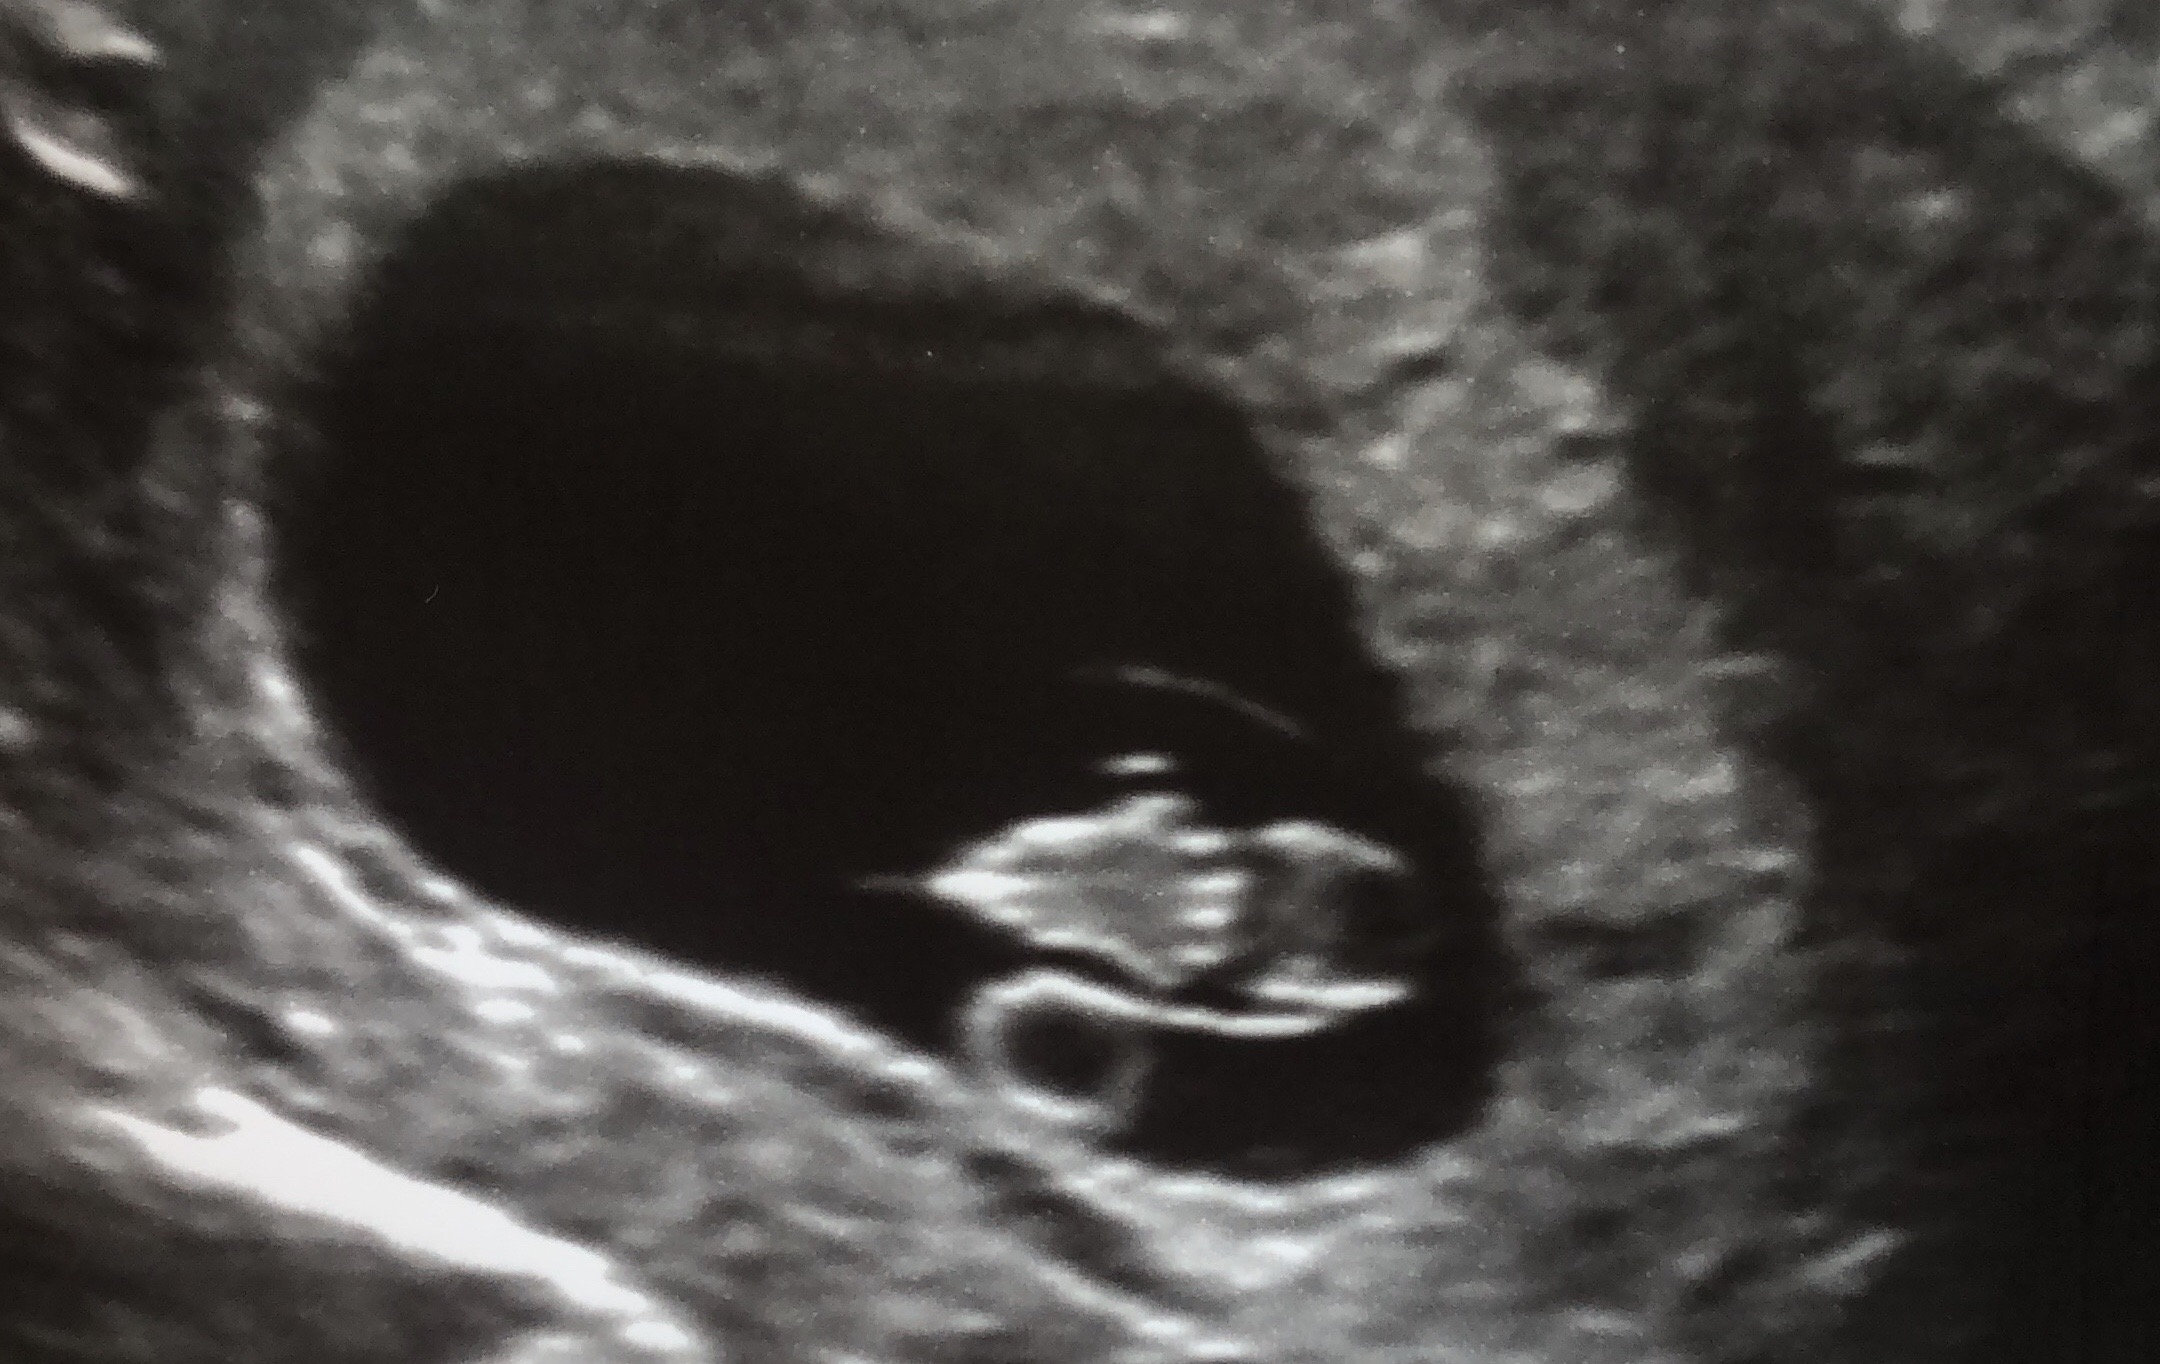

Measuring exactly what we thought it should be (7 weeks 6 days) and heartrate of 157 bpm. Definitely cried some happy tears seeing our little gummy bear. ❤ With my first pregnancy I MCd before we even got an ultrasound, so this was really my first experience seeing a baby on the monitor.